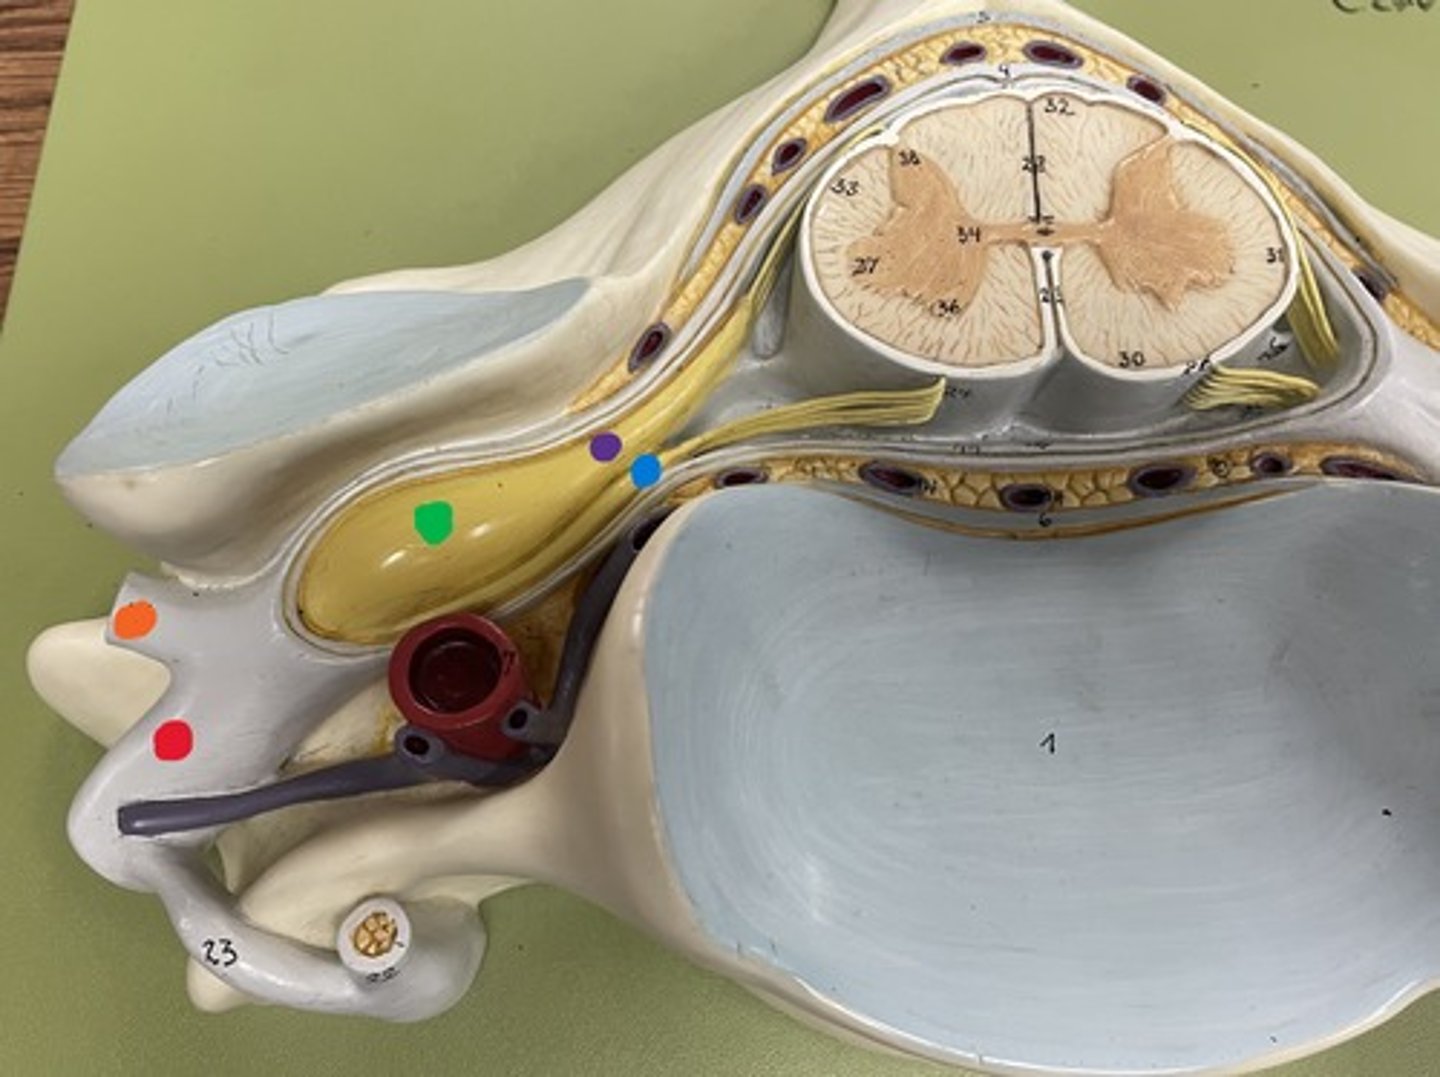

Cervical enlargement

Blue

Lumbar enlargement

Purple

Conus medullaris

Green

Cauda equina

Red

Filum terminale

blue

Epidural space

purple

Subdural space

between red and blue

Subarachnoid space

between red and green

Posterior root

purple

Posterior root ganglion

green

Posterior ramus

orange

Anterior root

blue

Anterior ramus

red